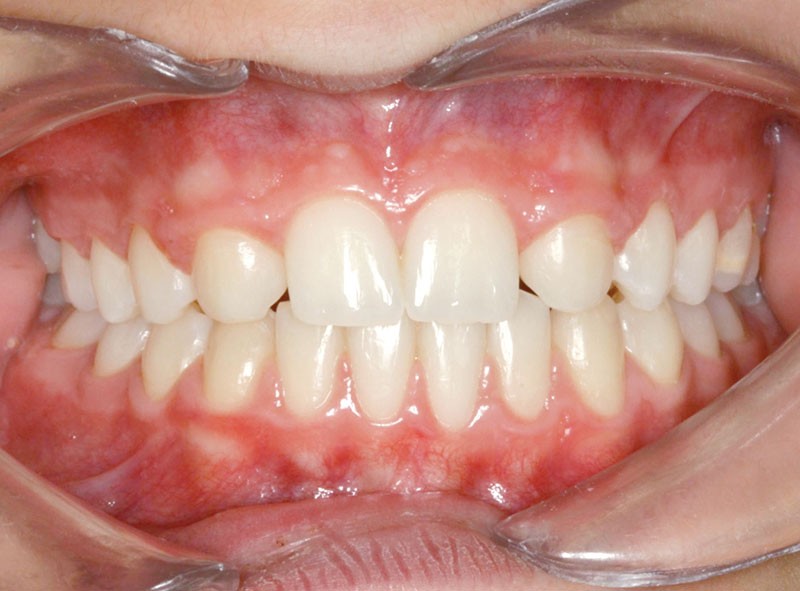

Le traitement orthodontique sans extraction à l’arcade mandibulaire a permis d’établir une occlusion de classe II thérapeutique équilibrée et un sourire harmonieux (fig. 4 et 5).

Une discrète coronoplastie par soustraction a adouci les contours des pointes cuspidiennes canines.